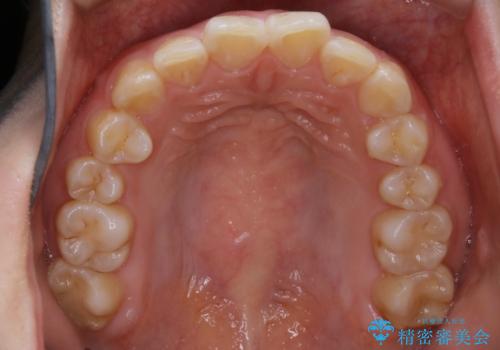

【非抜歯】ガタつきと歯軸を正して長持ちする歯へ

- 歯のガタつきと噛み合わせの改善を主訴に来院されました。

非抜歯で、少量の奥歯の移動と歯列の拡大・IPRを駆使して主訴を改善するための治療計画を立案しました。